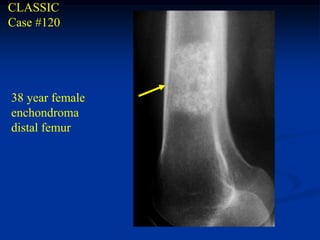

CLASSIC

Case #120

38 year female

enchondroma

distal femur